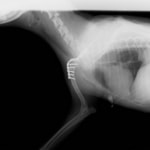

症例:トイプードル 9カ月齢

3ヵ月前より左前肢の跛行が認められるとのことで、来院されました。整形外科学的検査において、患肢の肘関節・肩関節重度の伸展制限が認められました。Xray検査において、左肩関節の内方脱臼、および肩甲骨関節窩の低形成と上腕骨頭の変形が認められました。

数か月に及ぶ慢性脱臼のため、関節面の低形成・摩耗のため整復手術による適切な再建は困難と判断し、切除関節形成術を実施しました。

術後3週間頃より、負重状態、歩行が改善しました。